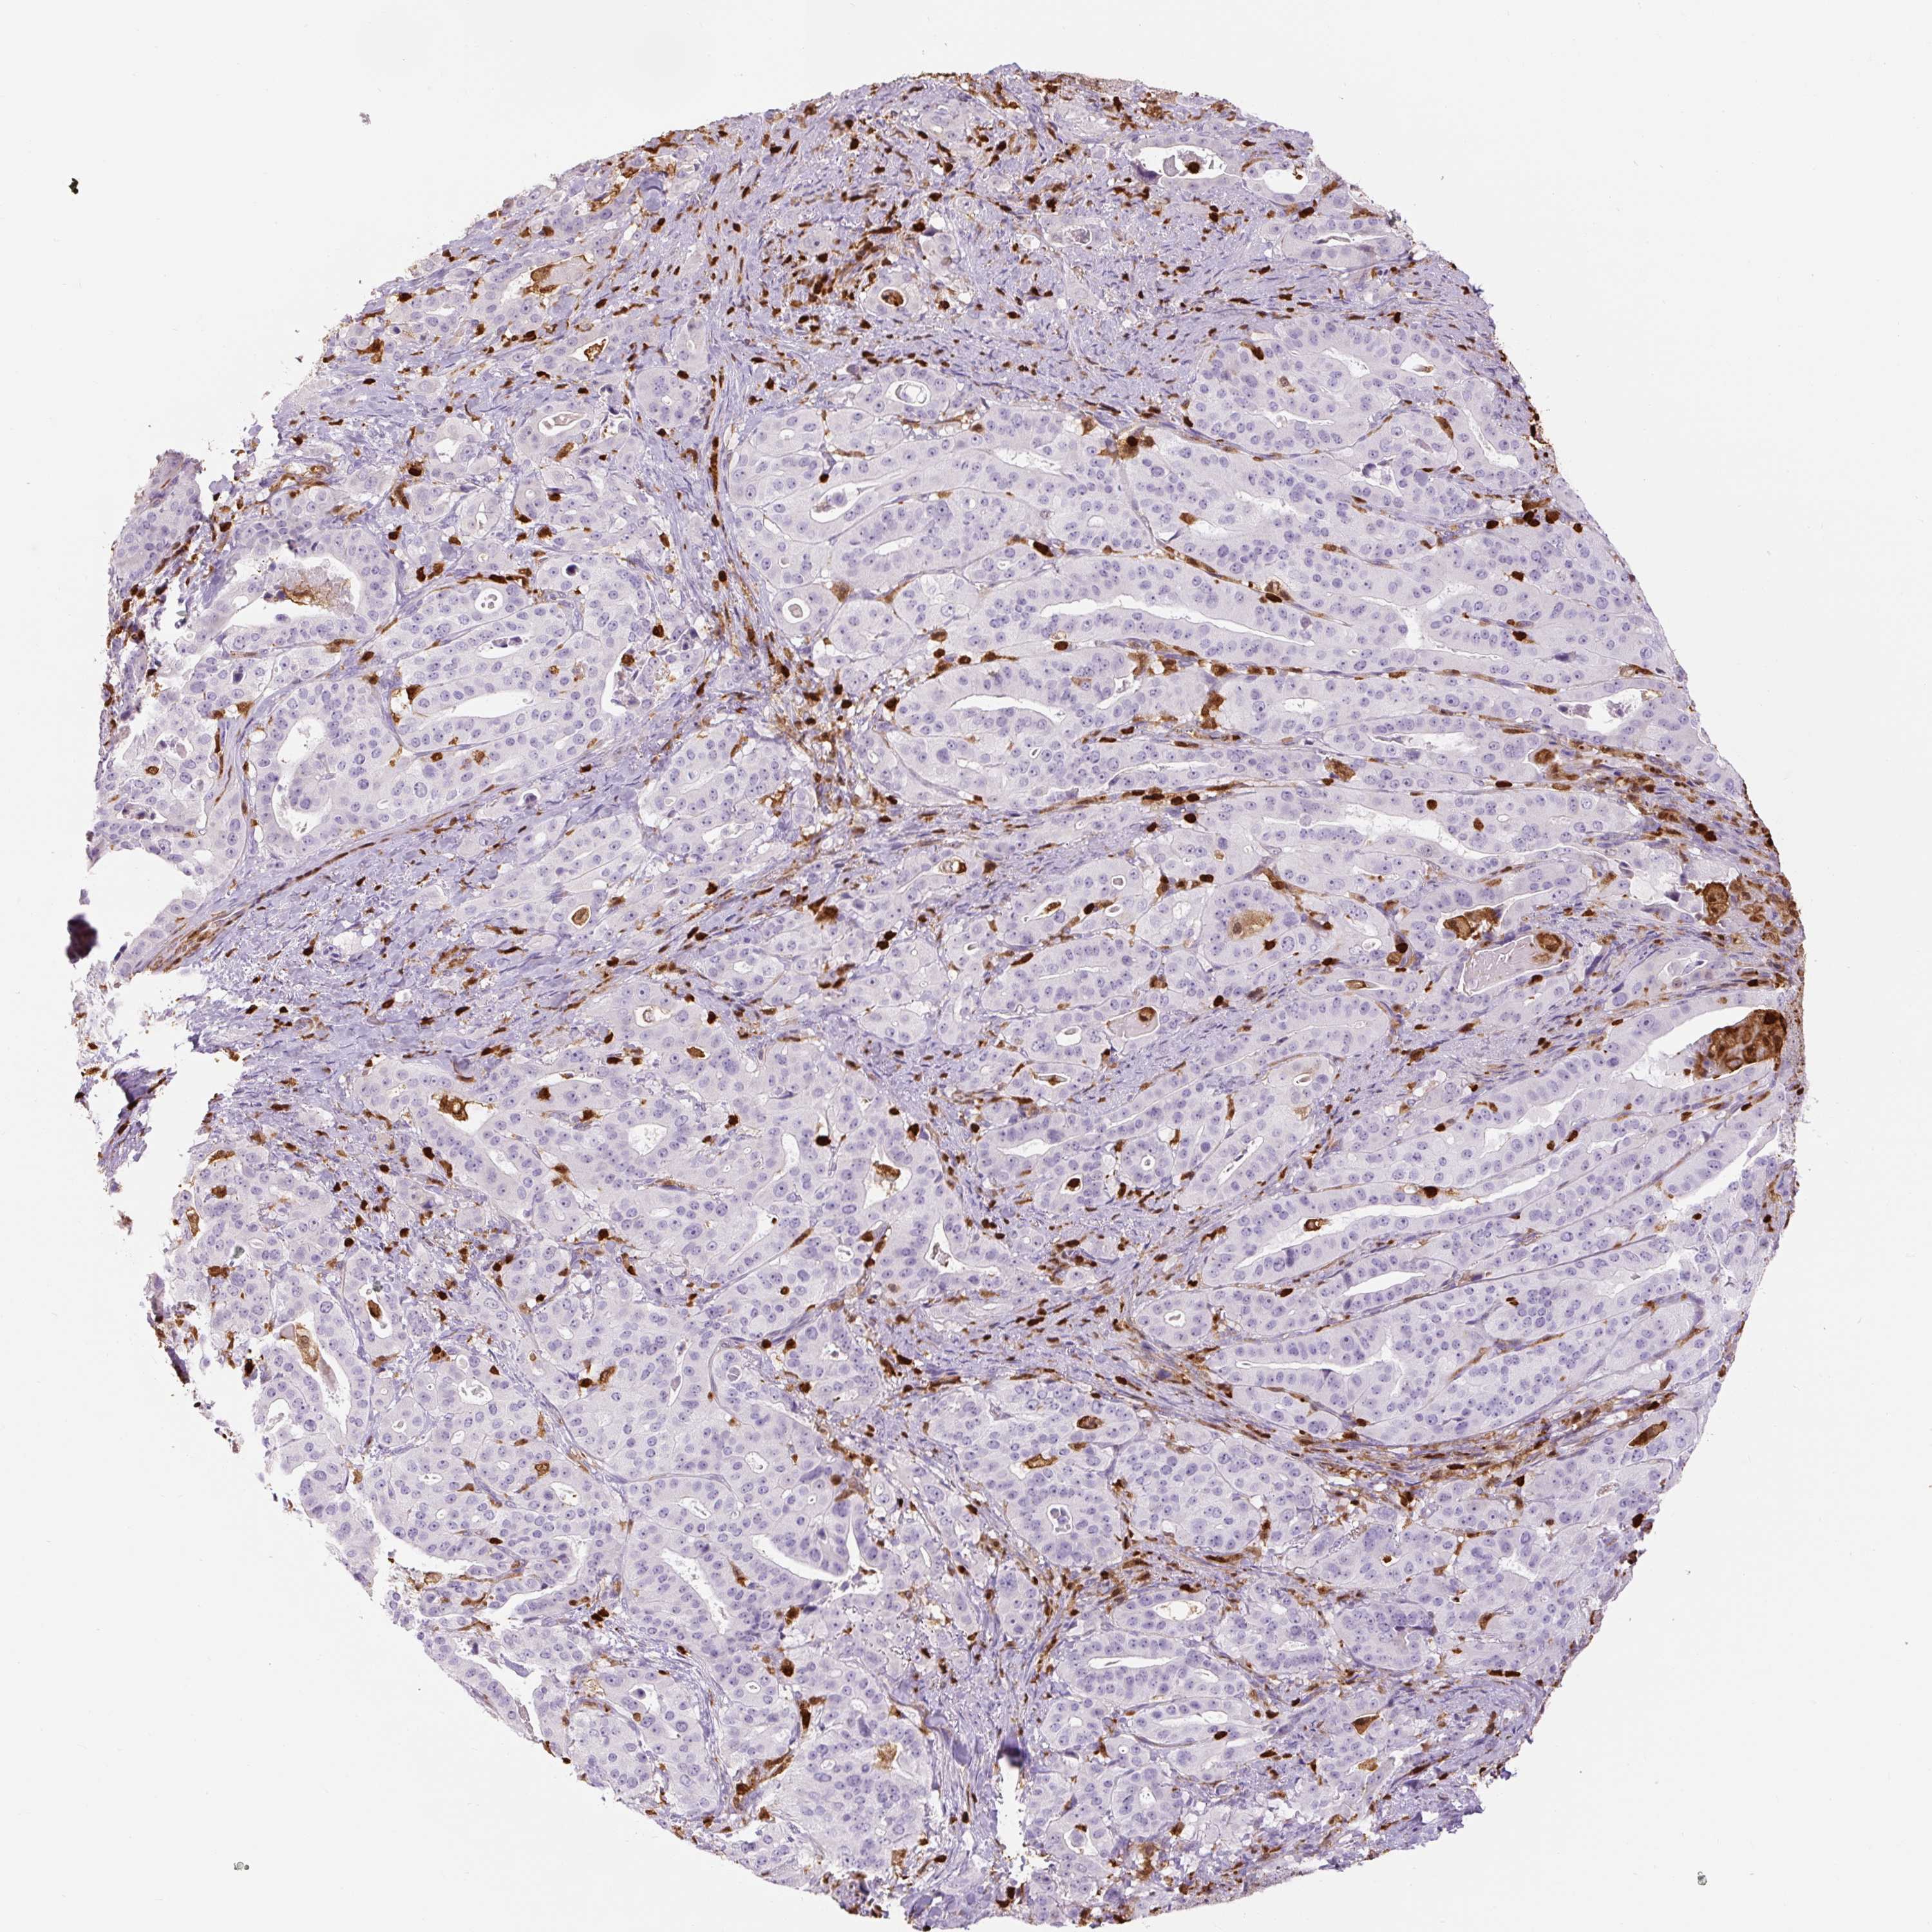

STOMACH CANCER - Protein expressioni

A mouse-over function shows sample information and annotation data. Click on an image to view it in a full screen mode. Samples can be filtered based on level of antibody staining by selecting one or several of the following categories: high, medium, low and not detected. The assay and annotation is described here.

Note that samples used for immunohistochemistry by the Human Protein Atlas do not correspond to samples in the TCGA dataset.

Antibody stainingi

Antibody staining in the annotated cell types in the current human tissue is reported as not detected, low, medium, or high, based on conventional immunohistochemistry profiling in selected tissues. This score is based on the combination of the staining intensity and fraction of stained cells.

Each image is clickable and will lead to virtual microscopy that enables deeper exploration of all samples and also displays staining intensity scores, fraction scores and subcellular localization as well as patient and tissue information for each sample.

HPA007973

CAB002618

CAB027387

CAB058698

CAB068227

CAB068228

Adenocarcinoma, NOS